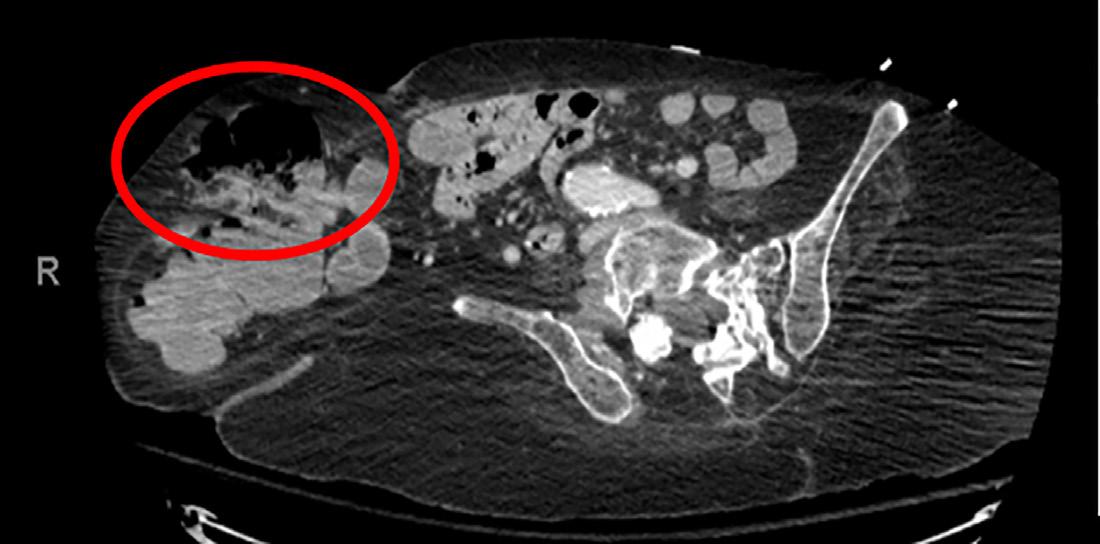

Immediately on arrival the patient was given one liter crystalloid with no improvement; therefore, one unit whole blood was given, followed by multiple units of emergency release packed red blood cells. While in the emergency department (ED), the patient’s ostomy bag was changed multiple times due to it being filled with dark red bloody stool. A CT abdomen and pelvis with intravenous (IV) contrast was performed but did not identify any obvious source of acute GI bleeding or acute pathology. Clear identification of the aortic graft occurred but showed no contrast extravasation or fistula (Image 1 and 2).

Image 1. Identification of the aortic graft above (circled red), demonstrating no contrast extravasation or fistula. CPC-EM Capsule